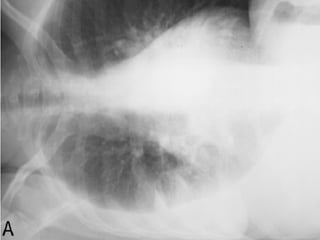

DIAGNÓSTICO POR  IMAGENOLOGÍA Oscar Asensio de la Cruza, Javier Blanco Gonzálezb, Antonio Moreno Galdóc, Javier  Pérez Fríasd, Antonio Salcedo Posadase, Lidia Sanz Borrellf Radiografía   PA y L :  hallazgo típico del derrame pleural:  obliteración del ángulo costofrénico posterior   que da una  imagen de menisco , bien notorio  >  de 175 ml de líquido .

RADIOLOGIA:  Detecta la presencia del derrame y sugiere su etiología  En la radiografía PA y lateral, el hallazgo típico del derrame pleural es la obliteración del ángulo costofrénico posterior (imagen de menisco). Un derrame masivo produce desviación contra lateral del mediastino; la causa más frecuente es la malignidad

RADIOLOGIA:  Se observan hallazgos atípicos: aplanamiento o desplazamiento en la cúpula  aumento de la distancia del diafragma a la burbuja gástrica (2 cm) u opacidad eliptoidea o &quot;pseudotumor&quot;. La proyección en decúbito lateral ayuda en casos de duda.  Importante cuando se va a puncionar (seguridad). .

Signo de Daimasseau Ellis Manual de Urgencias Hospital Toledo 2010 3ra ED